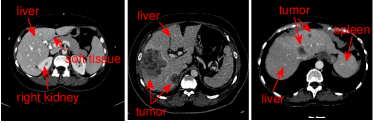

Refer to caption

Figure 1: Illustration of the challenges in automatic liver segmentation. The liver shares the similar intensity distributions with its surrounding organs (e.g., the right kidney and the spleen). The shape and appearance of the liver vary largely across subjects

Figure 4: Illustrations of the liver region located by 3D CNNs. The located liver region by 3D CNNs is in red with ground truth in blue. a 2D view in axial plane, b 2D view in coronal plane, c the surface distance error (mm) of 3D CNNs with the ground truth

Figure 5: Illustrations of the segmentation results by the proposed method. The contour of the segmentation result is in red with ground truth in blue. a 2D view in axial plane, b 2D view in coronal plane, c the surface distance error (mm) of the proposed with the ground truth

Figure 6: Illustrations of the role of the likelihood liver map. From the first column to the last, outcomes of graph cut without the likelihood liver map, convolutional neural networks and the proposed integrated model for two typical images are displayed respectively in red. The ground truth is in blue

Figure 7: 2D images of segmentation results of four challenging cases in axial, sagittal, and coronal planes with the ground truth in blue. The initial liver region generated by CNNs is in yellow and the final refined result is in red

To better understand the role of the learned liver likelihood map, Fig. 6 depicts the outputs of the graph cut without the liver likelihood map, 3D CNNs and the proposed method for two typical images in red. The ground truth segmentations drawn by experts are in blue. Obviously, incorporated with the liver likelihood map, the proposed model can achieve a better agreement with the ground truth.

Figure 7 illustrates our segmentation and manual delineations for four challenging cases in coronal, sagittal, and axial planes. The initial liver region generated by 3D CNNs is in yellow, the final refined result is in red and the manual delineation is in blue. The first column shows a case with highly inhomogeneous appearances. The last three columns display three representative livers containing tumors. Particularly, some tumors locate on the boundary, which makes it more difficult to automatically delineate the accurate boundary. As can be seen, 3D CNNs can detect the most liver region and the refinement model can obtain a higher agreement with the ground truth. Figure 8 depicts the corresponding 3D visualization results of 3D CNNs and the proposed method for the cases shown in Fig. 7. The 3D visualization of errors is based on the MSD error between the segmentation result and the ground truth. As can been seen, the MSD errors of the 3D CNNs for the four cases (from left to right) are 22.1 mm, 12.6 mm, 62.6 mm and 74.5 mm, respectively, while the MSD errors of the proposed model are 17.0 mm, 11.2 mm, 22.1 mm and 15.3 mm, respectively. Obviously, the proposed approach can obtain lower errors in terms of MSD.